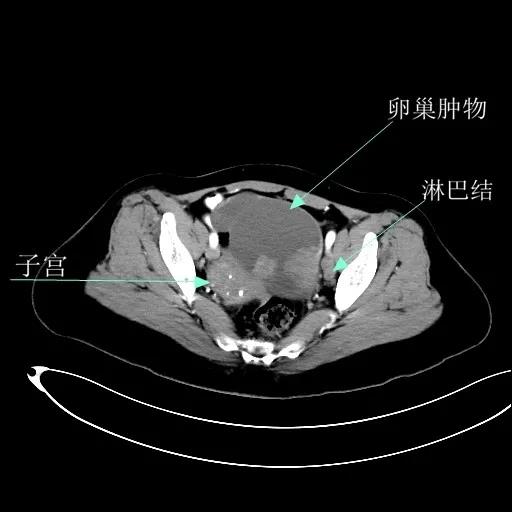

某患者因为“腹痛1周”而入院,外院B超提示子宫上方囊实性肿物,CT提示:左侧附件区占位,并盆腔及腹主动脉旁淋巴结转移。右肾动脉有右肾动脉及异位右肾动脉,其下均有肿大淋巴结。

妇科一病区严格遵循指南推荐,在影像学或探查淋巴结阳性的晚期卵巢癌中,若能达到满意减瘤,仍常规行盆腔及腹主动脉旁肿大淋巴结切除/清扫术(如下图举例)。通过前期初步统计分析,肠系膜下动脉至肾静脉下淋巴结转移阳性率为25%左右,在全部腹主动脉旁淋巴结转移患者中约占30%,显示了肾静脉下腹主动脉旁淋巴结清扫的价值。其对生存的影响有待进一步观察。